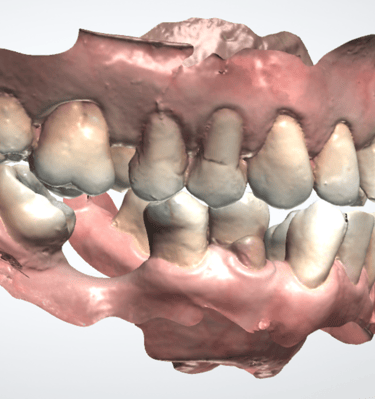

1. Registros iniciales: Modelo digital, tomografía dental y exámenes de laboratorio clínico.

2.Simulación y evaluación: Se planifica digitalmente el implante para evaluar cualquier riesgo.